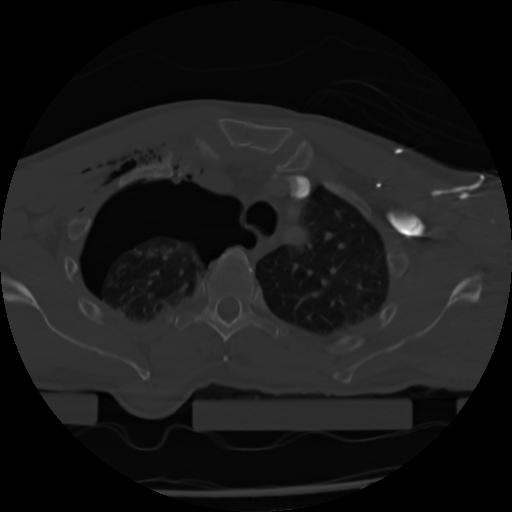

21 ANGIO,CE,Axial,3.0,ANGIO,,